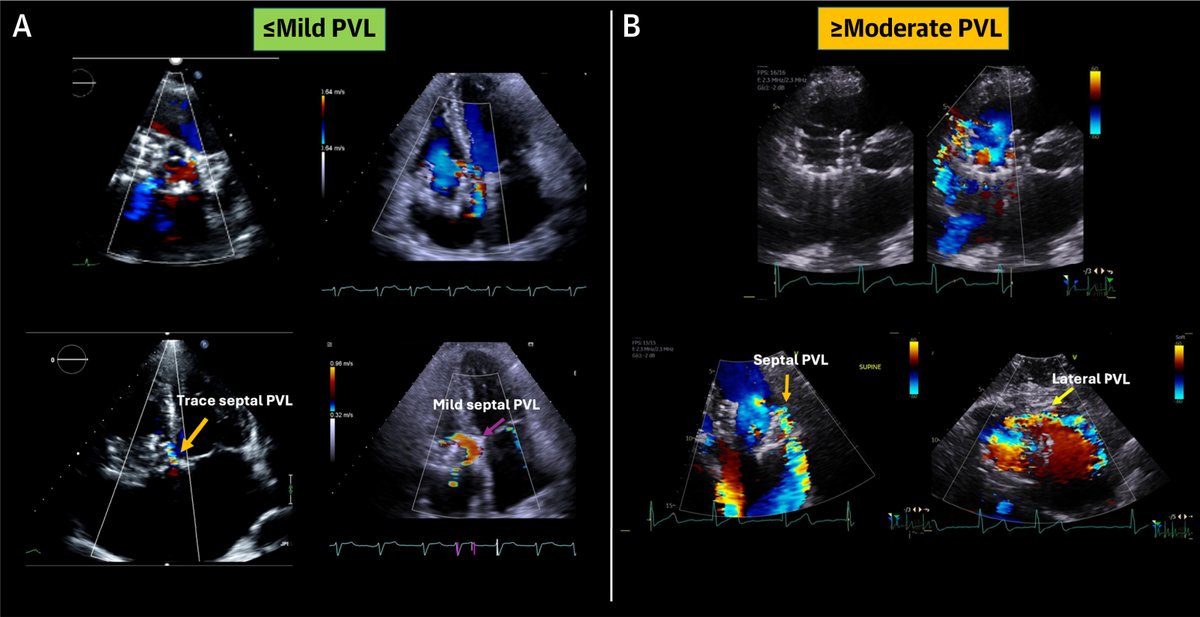

FANTASTIC MUST-READ #JACCIMG @JACCJournals SOTA review on Post #Evoque #TTVR Echo #TTE imaging. Comprehensive, practical! Download full paper here FREE for a LIMITED TIME! https://t.co/lfhJ0khJAw https://t.co/DgyCXnMOOF